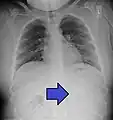

- AP X ray showing a 9mm battery in the intestines

- Lateral X ray showing a 9mm battery in the intestines